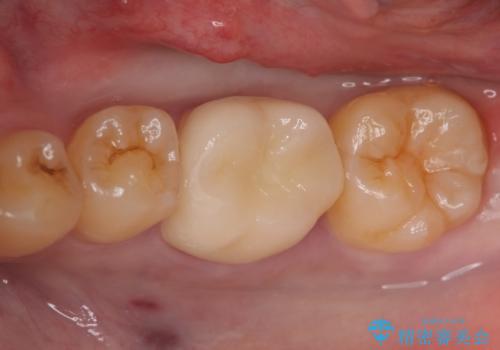

虫歯除去後、オールセラミッククラウンによる補綴を行いました。

- オールセラミッククラウン…¥100,000、仮歯…¥10,000費用は治療当時の料金となります

今回用いたオールセラミッククラウンはジルコニアフレームという白い素材の上にセラミックを盛っているため、審美性が非常に高いのが特徴です。

また、ジルコニアは人工ダイヤモンドの材料にも使われているほど高い強度を持っており、そのためオールセラミッククラウンは審美性だけでなく、奥歯やブリッジの補綴も可能とするクラウンです。